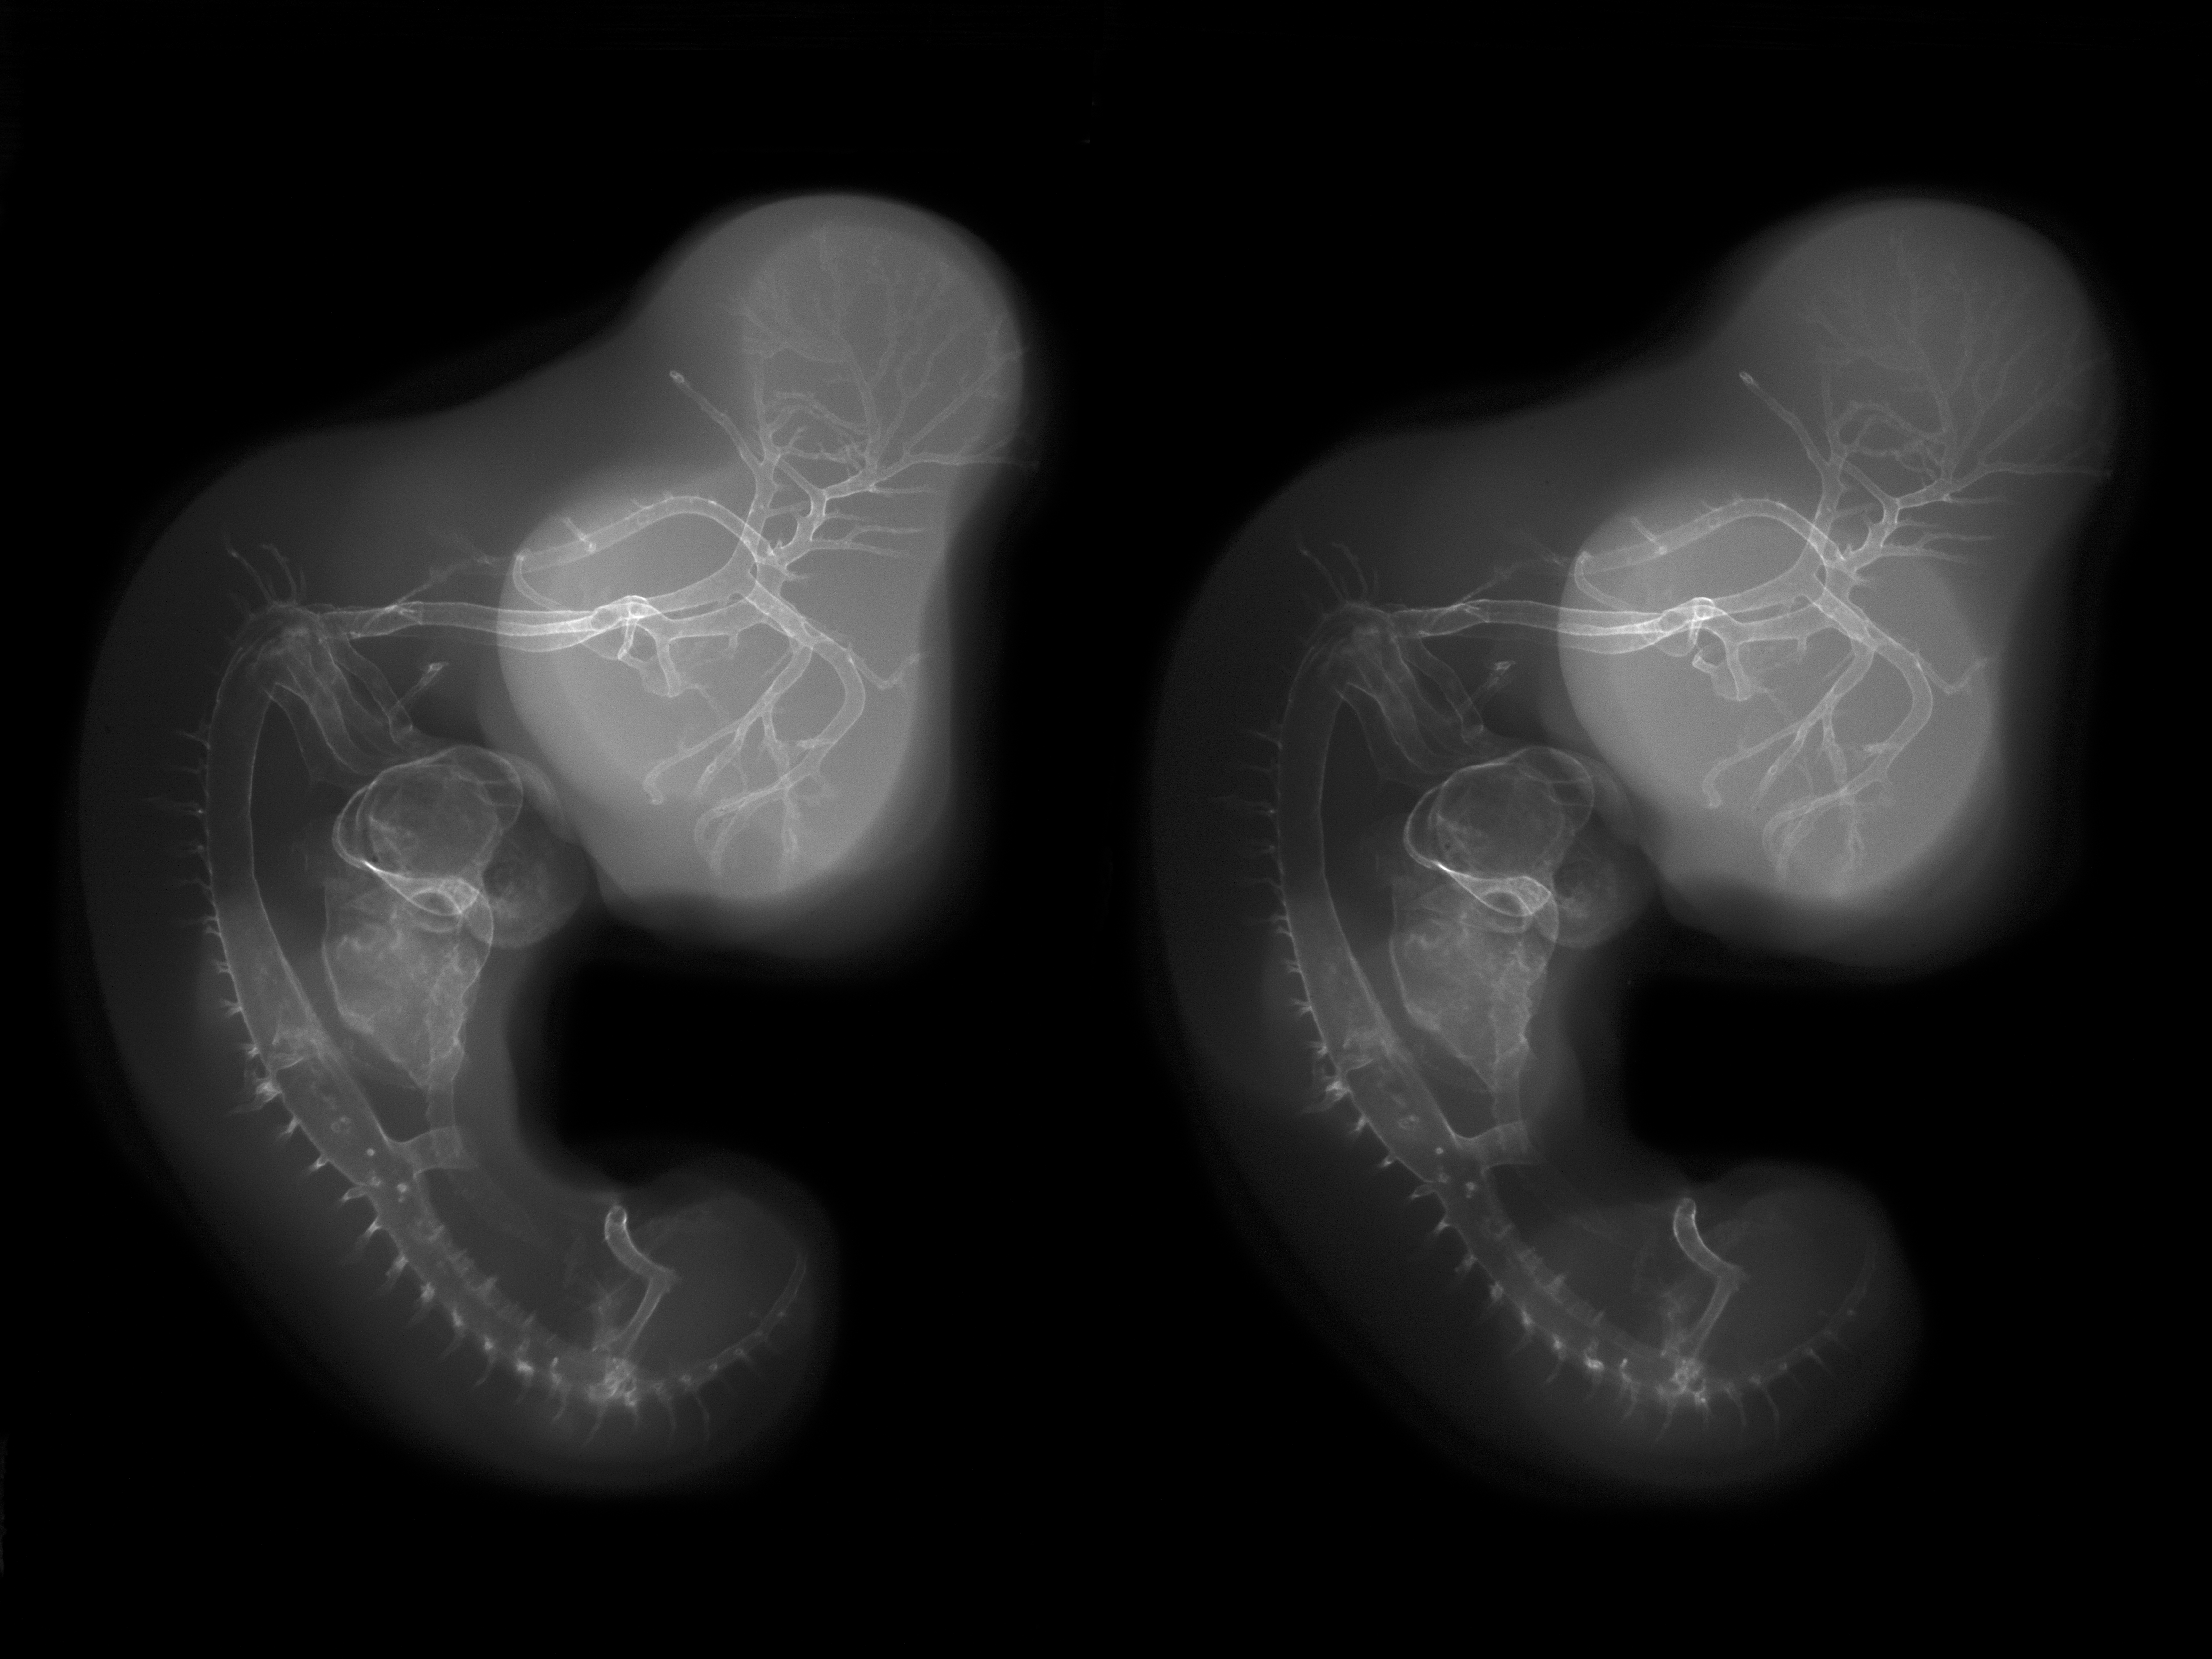

Chick Embryo Microangiography

Hamburger-Hamilton (HH) Stage 26 (approx. 5 days)

Stereo X-Ray Micrographs